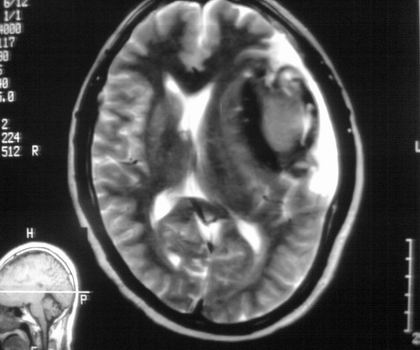

以下是引用muzi888在2008-4-30 17:21:00的发言:[br]脑外病变,蛛网膜下腔增宽,囊壁点状、环形钙化,增强扫描呈不均匀环状强化,考虑为囊性脑膜瘤可能性大,慢性脓肿、血肿机化、胆脂瘤不能除外。 [br] [br]支持!

以下是引用周战梅在2008-4-29 23:12:00的发言:[br]脑外病变,蛛网膜下腔增宽,囊壁点状、环形钙化,增强扫描呈不均匀环状强化,考虑为囊性脑膜瘤可能性大,慢性脓肿、血肿机化、胆脂瘤不能除外。